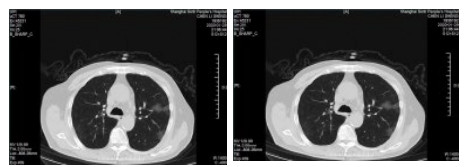

| 图 1 病例1,男性,65岁,沪籍,否认武汉流行病学接触史,发病前2周内每天有大型医院陪护史及疲劳史,既往体健,发热1 d入院,体温38.5℃,无咳嗽症状,无鼻塞,流涕,血白细胞总数及淋巴计数正常,甲乙型流感病毒筛查阴性,新型冠状病毒核酸检测阳性。肺部CT提示双肺多发磨玻璃结节,病灶贴近胸膜,局部小叶间隔增厚,炎症沿支气管血管走向分布,散在小结节影及纤维条索影 Fig 1 Case 1, male, 65 years old, born in Shanghai, denied the history of epidemic exposure of Wuhan. He had a history of accompanying in hospital every day and fatigue in the first two weeks before the onset of the disease. He was hospitalized one day after the onset of fever, with a body temperature of 38.5 ℃, no cough, no nasal obstruction and runny nose, normal WBC and lymph count, negative influenza A and B virus screening, and positive novel coronavirus nucleic acid test. Lung CT showed multiple ground glass nodules in both lungs. The focus was close to pleura, the interlobular septum was thickened, the inflammation distributed along the direction of bronchi and blood vessels, scattered in small nodule shadow and fibrous cord shadow |